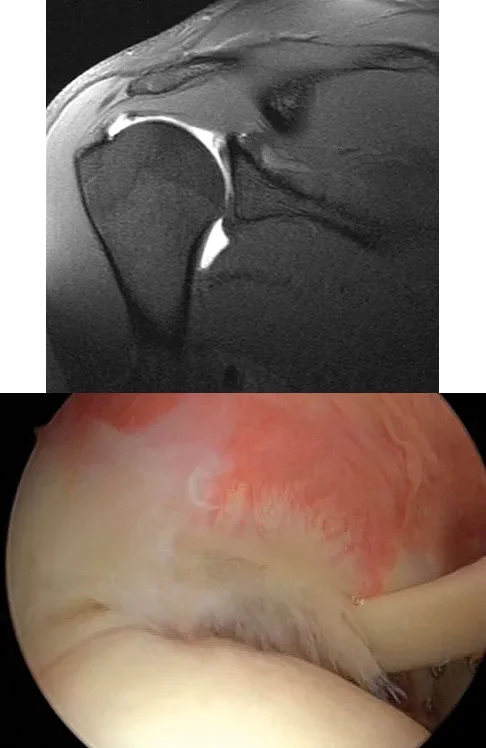

A 21-year-old collegiate pitcher undergoes shoulder arthroscopy for chronic pain. The image shows a Type I SLAP lesion. Which of the following best describes the pathologic anatomy of a Type I SLAP lesion?

Explanation

Correct Answer: A

A Type I SLAP lesion is characterized by fraying and degeneration of the superior labrum, but the biceps anchor remains firmly attached to the glenoid. Treatment typically involves simple debridement. Type II involves detachment of the superior labrum and biceps anchor. Type III is a bucket-handle tear of the labrum with an intact biceps anchor. Type IV is a bucket-handle tear extending into the biceps tendon.

A 21-year-old collegiate pitcher presents with chronic shoulder pain that has failed to improve with rest and physical therapy. An arthroscopic view from the posterior portal is shown. Probing reveals fraying of the superior labrum, but the biceps anchor is firmly attached to the superior glenoid tubercle. Which of the following best describes the Snyder classification and the most appropriate management for this lesion?

Correct Answer: Type I; arthroscopic debridement

The arthroscopic image demonstrates a Type I SLAP (Superior Labrum Anterior and Posterior) lesion, which is characterized by fraying and degeneration of the superior labrum with an intact biceps anchor. The appropriate treatment for a Type I SLAP lesion is simple arthroscopic debridement. Biceps tenodesis or tenotomy is not indicated because the biceps anchor is stable. Type II lesions involve detachment of the superior labrum and biceps anchor and are typically treated with repair. Type III lesions are bucket-handle tears of the labrum with an intact biceps anchor, and Type IV lesions are bucket-handle tears that extend into the biceps tendon.

A 21-year-old collegiate pitcher presents with shoulder pain. Arthroscopy reveals fraying of the superior labrum with an intact biceps anchor, as shown in the provided image. Which of the following is the most appropriate management for this specific lesion?

Correct Answer: Arthroscopic debridement

The image and description correspond to a Type I SLAP lesion (fraying of the superior labrum with an intact biceps anchor). The appropriate treatment is simple debridement. Biceps tenodesis or release is not indicated because the biceps tendon and anchor are intact. There is no indication for labral repair or capsulorrhaphy.

A 25-year-old man presents with right shoulder pain. An arthroscopic view from the posterior portal viewing the articular surface of the supraspinatus is shown. The lesion is identified as a partial articular-sided supraspinatus tendon avulsion (PASTA). If this lesion involves greater than 50% of the tendon thickness, which of the following is an accepted surgical management strategy?

Correct Answer: Transtendon arthroscopic repair

The images demonstrate a PASTA lesion (Partial Articular-Sided Tendon Avulsion). When a PASTA lesion involves greater than 50% of the tendon footprint thickness, surgical repair is generally indicated. An accepted and common technique is a transtendon arthroscopic repair, which allows the surgeon to secure the articular-sided tear down to the footprint without taking down the intact bursal-sided tissue. This preserves the intact lateral fibers of the rotator cuff while restoring the medial footprint anatomy.